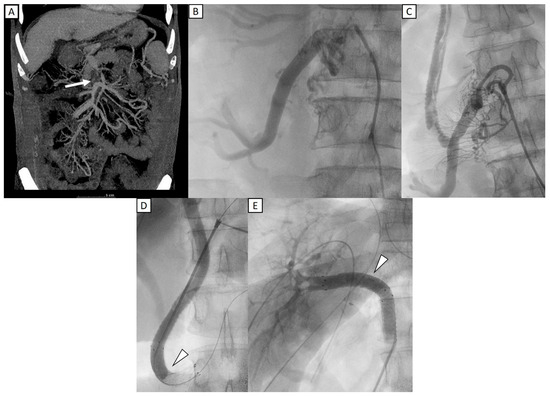

Applying Intraoperative Portal Venography in Liver Transplantation Vascular Surgery

Background/Aim: Adequate portal inflow is essential for liver graft regeneration following transplantation. Intraoperative portal venography (IOPV) provides real-time assessment of portal vein patency, stenosis, thrombus formation, and portosystemic collaterals. In addition to imaging, portal vein pressure gradient (portal vein pressure minus inferior vena [...] Read more.

Background/Aim: Adequate portal inflow is essential for liver graft regeneration following transplantation. Intraoperative portal venography (IOPV) provides real-time assessment of portal vein patency, stenosis, thrombus formation, and portosystemic collaterals. In addition to imaging, portal vein pressure gradient (portal vein pressure minus inferior vena cava pressure) was also measured. This study assessed the impact of IOPV on surgical decision-making and post-transplant outcomes to establish criteria for patient selection. Methods: From November 2016 to November 2024, 34 liver transplant patients with portal inflow insufficiency (flow velocity < 10 cm/s), large shunts (>1 cm), or portal vein thrombosis underwent IOPV. Of the patients, one received deceased donor liver transplantation (DDLT), and the others received living donor liver transplantation (LDLT). Preoperative computed tomography (CT) and ultrasound (US) assessed portal vein patency, thrombus, and shunts. Postoperative US and CT monitored portal flow and graft regeneration. Results: IOPV influenced surgical planning in all cases, leading to shunt ligation or stenting, and improved portal vein flow velocity from 6.3 (IQR, 0–9.0) to 30.8 (IQR, 22.2–36.7) cm/s (p < 0.001). Adequate inflow was achieved in 32 patients, 2 had persistent low flow or occluded flow owing to severe adhesion after transplant and failure to close large collateral veins. Graft regeneration ranged from 104% to 255% within a year. Conclusions: IOPV is a valuable tool in liver transplantation vascular surgery, optimizing surgical strategies and portal inflow. Early integration into routine practice may improve graft outcomes. Further prospective, longitudinal research is needed to refine patient selection and assess long-term benefits. Full article

Figure 1